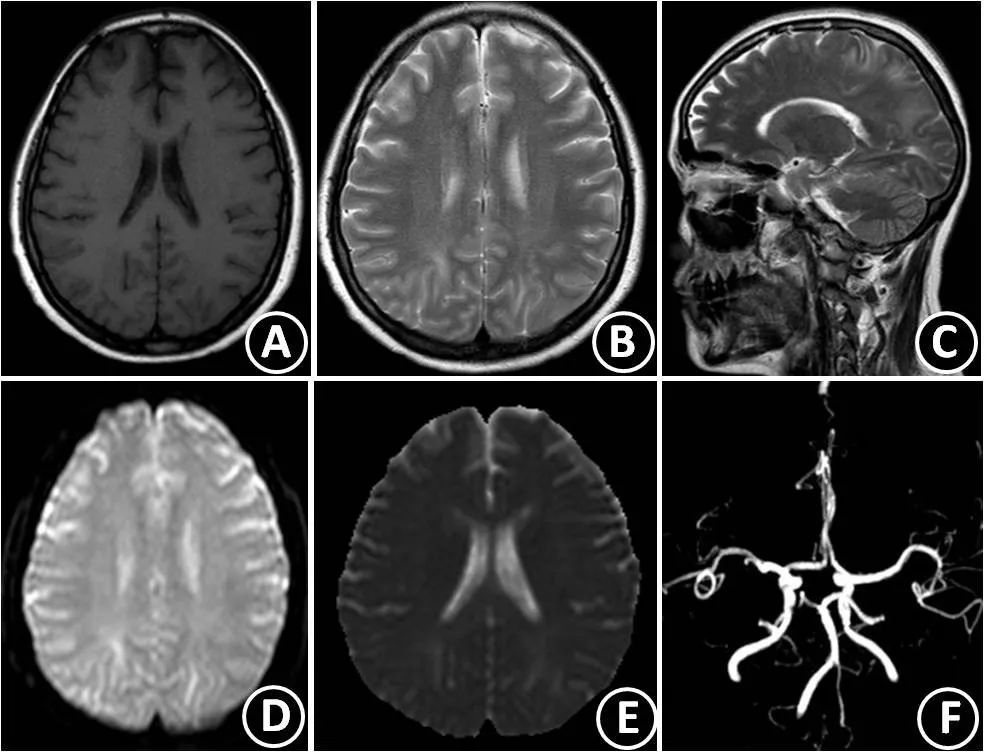

49岁女性,突然醒来出现言语不清。最初CT报告左侧MCA区域脑梗死伴左侧MCA高密度(A),MRI显示非强化(B)、T2-FLAIR高信号(C)的膨胀性病灶伴弥散增加(D-DWI,E-ADC)。

活检为间变性少突胶质细胞瘤。

图8:瘤卒中(源自曹勇军教授讲课PPT)

图9:头颅CT可见双侧枕顶叶低密度灶(A),头颅MRI示双侧枕叶在T1WI像呈低信号(B),DWI像呈等高信号(D),T2WI(C)、ADC(E)和FLAIR(F)像呈高信号。(源自曹勇军教授讲课PPT)

用甘露醇降压及其它对症治疗后,复查头颅MRI复查示双侧枕叶在T1WL(A)像的低信号,T2WI(B和C),DWI(D)和ADC(E)像的异常信号消失,TOF-MRA示颅内动脉未见异常(F)。

图10:治疗后复查影像学检查结果(源自曹勇军教授讲课PPT)